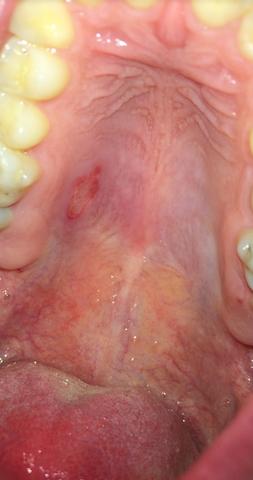

Diese wird genau untersucht. Eine Entzündung am Gaumen fällt meist durch eine schmerzhafte Schwelllung und Rötung auf. Beschwerden am gaumen bei zahnschmerzen hintergrund können zahnschmerzen sein die sich auf den gesamten mund rachen bereich ausdehnen und damit auch den gaumen betreffen können einleitung eine entzündung am gaumen fällt meist durch eine schmerzhafte schwelllung und rötung auf.

Die sorgt dafür dass aus dem Zucker im Honig Wasserstoffperoxid. Zu unterscheiden sind die Entzündung an der Schleimhaut des Gaumens selbst und Entzündungen am Zäpfchen den Mandeln im Gaumensegel.

Recurrent aphthous stomatitis oral apthous ulcers sind kleine weiße oder rote offene Stellen oder Geschwüre der Mundschleimhaut der Zunge oder des Gaumens. Die sorgt dafür dass aus dem Zucker im Honig Wasserstoffperoxid. Entzündung am Gaumen - Dr-Gumpert. Diese kann aufgrund von Verletzungen Infektionen allergischen Reaktionen oder gar Verbrennungen auftreten. Eine Entzündung am Gaumen fällt meist durch eine schmerzhafte Schwelllung und Rötung auf. Beschwerden am Gaumen bei Zahnschmerzen Hintergrund können Zahnschmerzen sein die sich auf den gesamten Mund-Rachen-Bereich ausdehnen und damit auch den Gaumen betreffen können Einleitung Eine Entzündung am Gaumen fällt meist durch eine schmerzhafte Schwelllung und Rötung aufDiese kann aufgrund von Verletzungen Infektionen allergischen. Ich hoffe ich bin im richtigen Forum. Der Begriff kommt aus dem Griechischen und bedeutet Schwämmchen. Beim Kauen oder bei Kontakt mit Fruchtsäure.